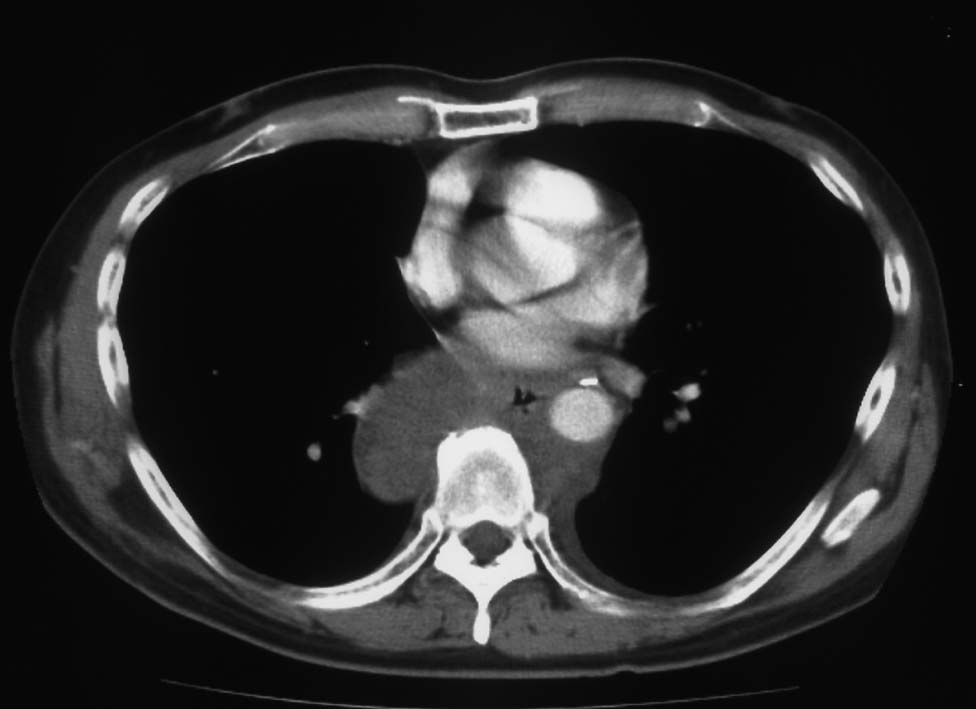

5ヵ月後右主気管支を圧迫しほとんど閉塞する巨大な腫瘍を認めた. 他院で緊急放射線療法および化学療法を行うが効果なし. 腫瘍切除+右肺上葉切除をおこない肉眼的には腫瘍は完全切除できた. 病理診断は非典型的であるが malignant SFT. 当院に再入院, radiation therapyをおこなう. 効果乏しく, 腫瘍は進行し呼吸不全で永眠される.

胸腔鏡下ブラ切除術5ヵ月後, 縦隔腫瘤で再発. 他院で腫瘍切除+右肺上葉切除を施行. 肉眼的には腫瘍は完全に切除できた.

初診から11ヵ月, 胸部つかえ感出現. CTで気管分岐部から横隔膜食道裂孔を通り, 腹腔内へ進展, 食道および大動脈を囲繞する巨大な腫瘍が再発した. 他院での抗がん剤感受性テストの結果より, CDDP+5FUによる化学療法がおこなわれたが効果乏しく全身状態悪化. 呼吸不全が進行し初診より約1年の経過で永眠された.